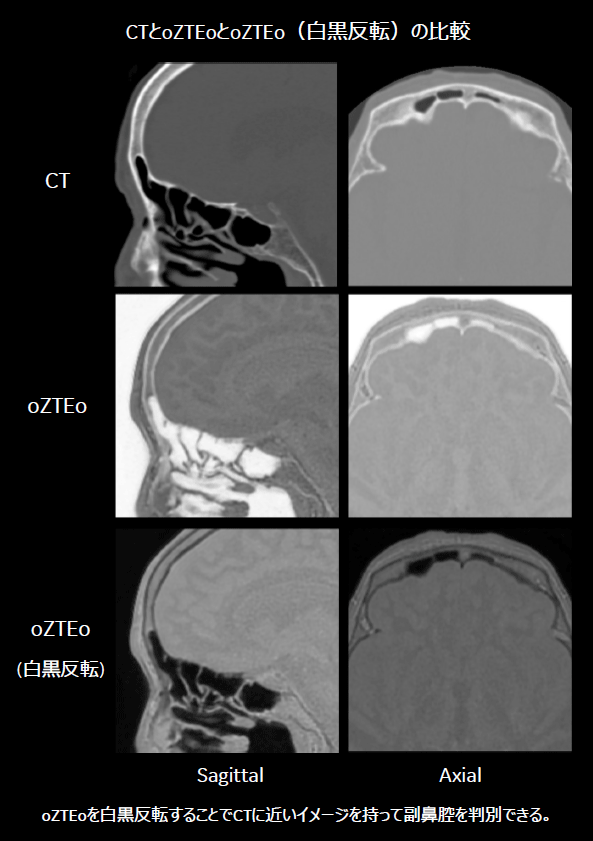

従来は、造影剤を用いたCT検査にて、骨、動脈、静脈を3D画像化し術前シミュレーション用として提供している。また、当院では術中感染リスクの観点より、副鼻腔、特に前頭洞の画像化も同時に行っている。oZTEoのが使用可能になったことにより、MRIのみにて骨(oZTEo)、動脈(3D-TOF)、静脈(3D-PC)の作成が可能となった。また副鼻腔の描出に関しては、CTと比較してもその描出能に問題はなく、比較的容易にVR作成可能であることが分かった。これらのことから、追加の撮像時間(3シーケンス撮像のため)を要するが、造影剤が不要であるという利点を活かしたMRI術前シミュレーション用フュージョン画像の提供が可能となる。